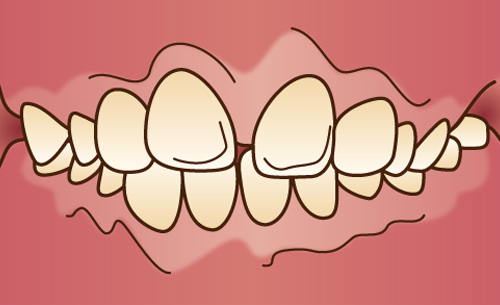

歯並びがでこぼこな乱ぐい歯、犬歯が前に突き出た八重歯などをいいます。顎が小さいと歯が生える十分なスペースがないため、歯と歯が重なり合って、叢生が生じると考えられています。